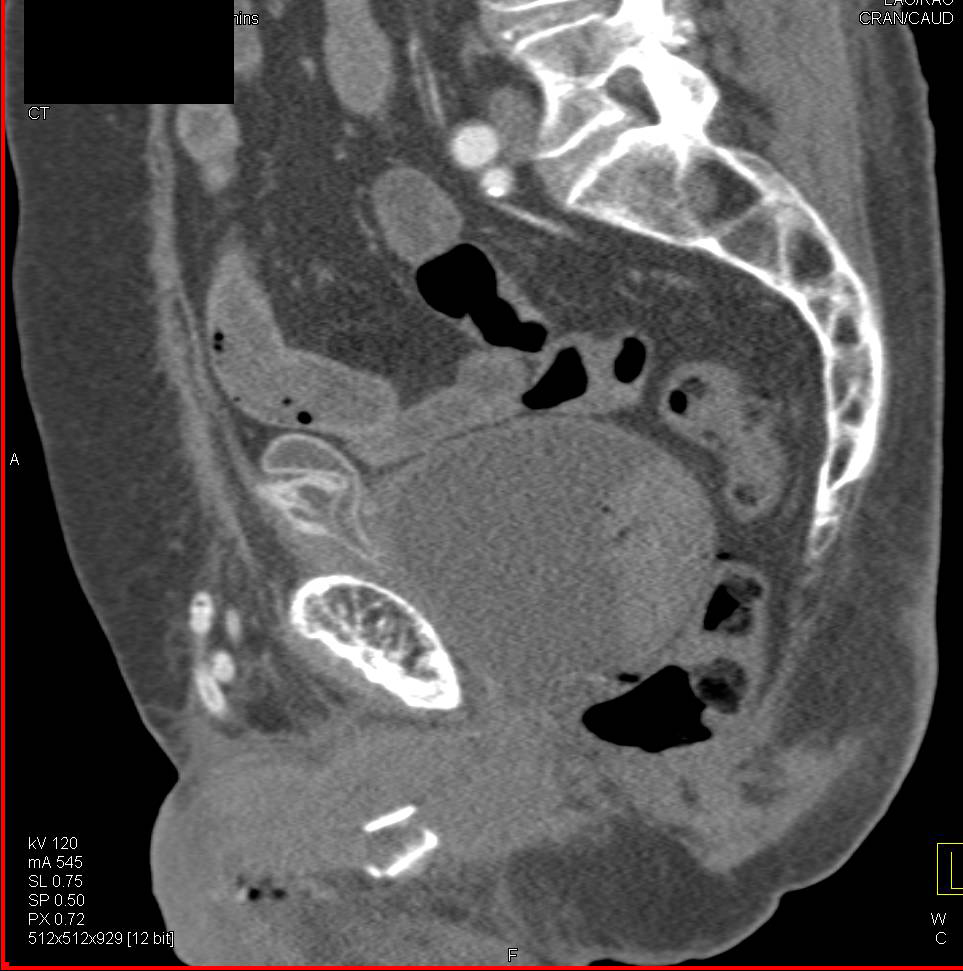

Ct scan of the abdomen reveals a distended urinary bladder (B) and... Download Scientific Diagram Ct Anatomy Of Urinary Bladder The urinary bladder is a muscular sac in the pelvis, just above and behind the pubic bone. Magnetic resonance imaging (mri) is inherently suited. A computed tomography (ct) urogram is a useful diagnostic tool for detecting conditions that affect your urinary system. Ct scans with contrast are used to evaluate masses (parenchymal phase) and the collecting system (excretory phase). The. Ct Anatomy Of Urinary Bladder.